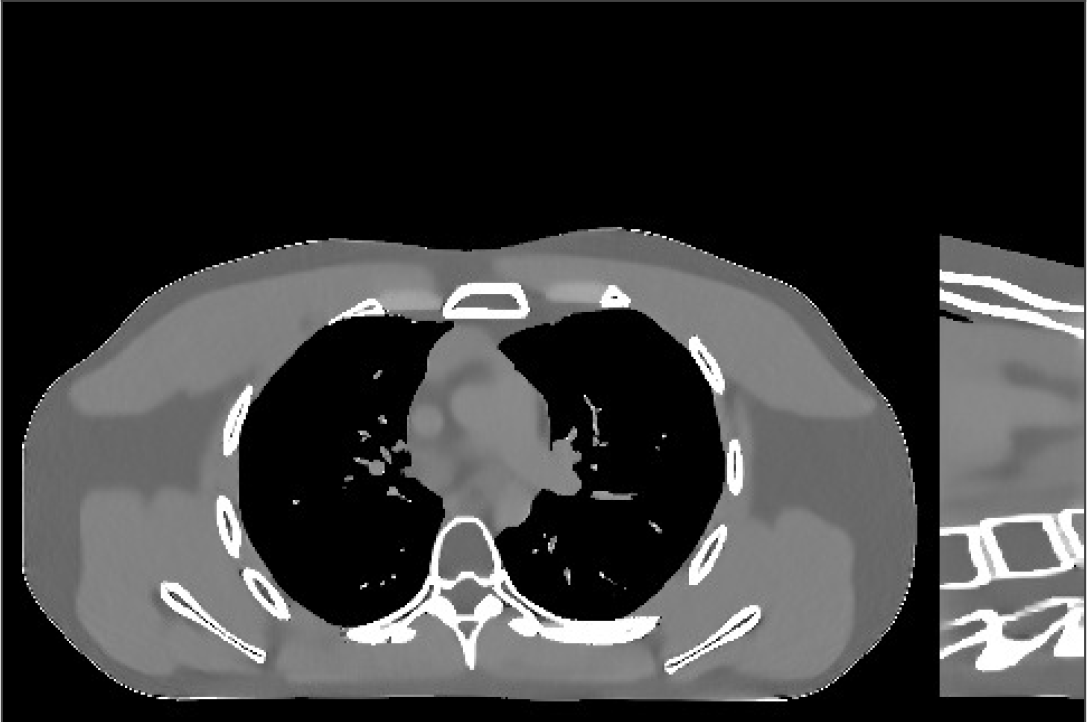

Fig.Β 7 shows the reconstructions (shown for the central axial plane in the 3D volume) for FDK (provided by GE Healthcare), PWLS-EP (corresponds to Fig.Β 8(a)), and PWLS-ULTRA with (corresponds to Fig.Β 9(a)). The PWLS-ULTRA reconstruction has lower artifacts and noise. Moreover, the image features and edges are better reconstructed by PWLS-ULTRA than by PWLS-EP or FDK.

Fig.Β 8 shows the reconstructions (shown for the central axial, sagittal, and coronal planes in the 3D volume) for PWLS-EP with different regularization strengths , denoted as a multiplicative factor of the parameter value in Fig.Β 7. Fig.Β 9 shows the reconstructions for PWLS-ULTRA (with patch-based weights) with different parameter combinations. For the sagittal and coronal planes, we show the central out of axial slices. Larger regularization strengths would achieve more noise reduction but simultaneously lower spatial resolution in PWLS-EP and PWLS-ULTRA, e.g., compare Fig.Β 8 and Figs.Β 9(a) and (d). Larger values of would achieve lower sparsities and more noise reduction but potentially oversmooth the image, e.g., compare Figs.Β 9(c) and (d). Small values of may introduce additional spurious noise in the PWLS-ULTRA reconstruction (compare Figs.Β 9(a) and (b)). Fig.Β 11 shows profiles of chest reconstructions (plotted from the central axial slice) for the PWLS-EP and PWLS-ULTRA methods. The profile locations are shown in green lines in Fig.Β 7. Both PWLS-EP with regularization strength X and PWLS-ULTRA (with patch-based weights) in Fig.Β 9(a) have lower noise than the PWLS-EP with regularization strength X. Though the spatial resolution of PWLS-EP with regularization strength X is close to PWLS-ULTRA in the selected soft-tissue regions, PWLS-ULTRA reconstructs bone and spine areas with higher resolution, and preserves small features better (compare the zoomed-in areas in Fig.Β 8 and Fig.Β 9).